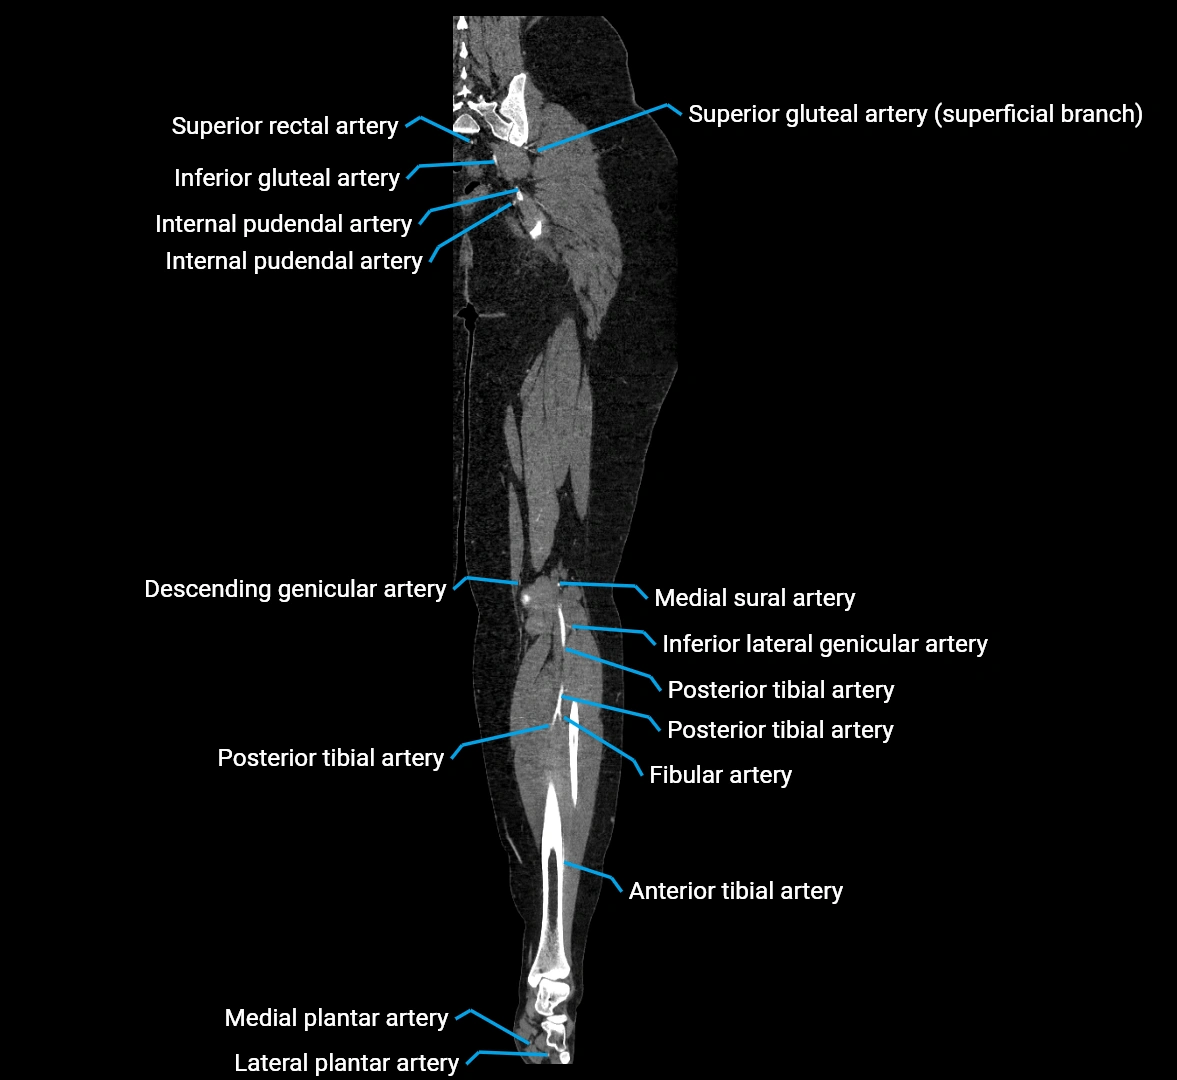

CT images

image